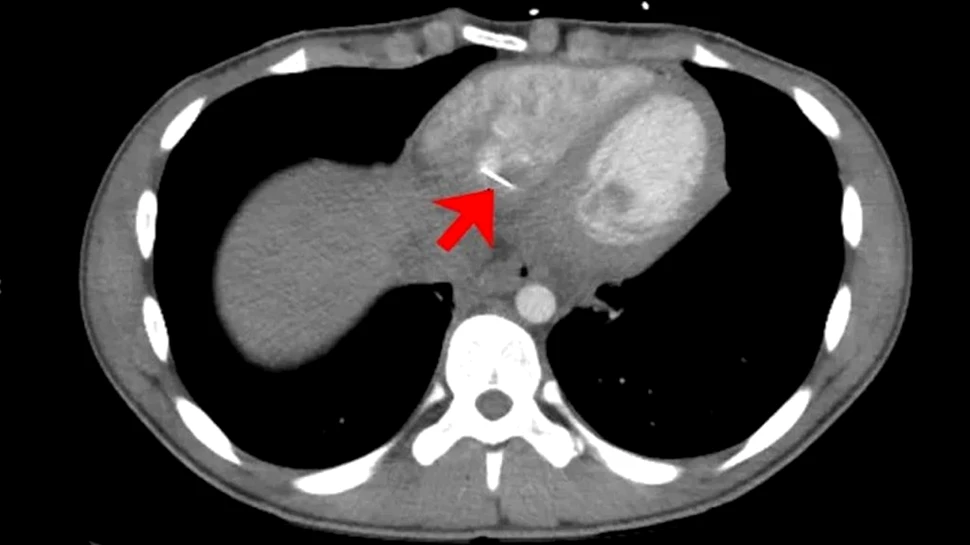

Credit foto: Mathews et al., TJEM, 2020

O scanare computerizată a pieptului său a arătat că există un obiect „străin liniar metalic” în inima sa, după cum arată raportul medical. Obiectul avea o lungime de aproximativ 3,5 centimetri și ieșea din ventriculul drept al inimii, camera inferioară dreaptă a inimii care pompează sângele câtre plămâni.